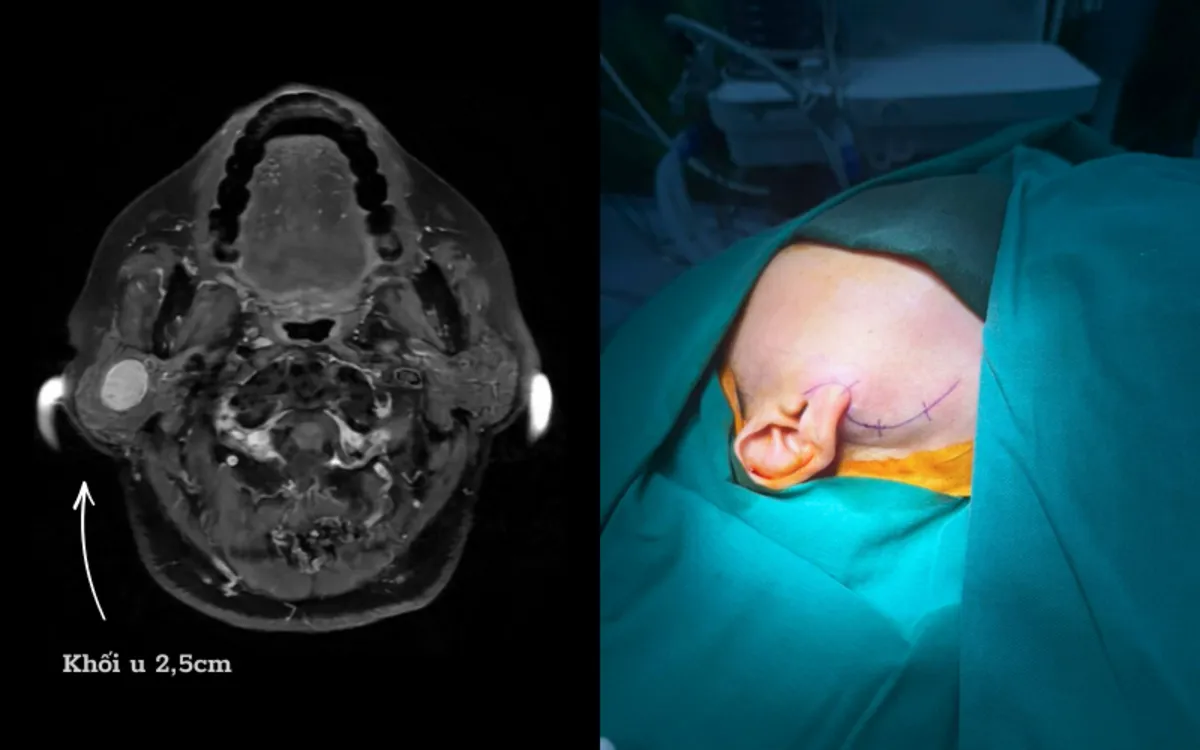

Trường hợp bệnh nhân D. là ví dụ điển hình, người bệnh phát hiện khối u tuyến mang tai phải từ nhiều năm trước, có biểu hiện sưng lệch vùng góc hàm, thỉnh thoảng đau tức. Dù đã được chỉ định phẫu thuật từ sớm nhưng bệnh nhân liên tục trì hoãn do lo ngại có nguy cơ liệt mặt sau mổ.

U tuyến nước bọt mang tai của chị D có vị trí phức tạp

Ca phẫu thuật của bệnh nhân D. kéo dài khoảng 3 giờ, kết quả thành công tốt đẹp. Khối u được lấy trọn vẹn mà không cần cắt bỏ toàn bộ tuyến mang tai. Sau mổ, người bệnh D. hồi phục tốt, không ghi nhận liệt dây thần kinh mặt. Đặc biệt, gương mặt cân đối, không méo lệch, chức năng vận động và yếu tố thẩm mỹ được bảo tồn nguyên vẹn.